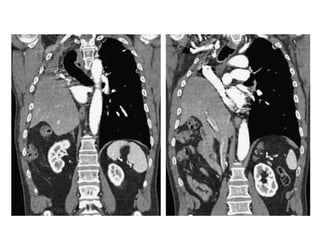

Caso Clínico

• Fem. 17 años. APP:

Amputación del MII por

rabdomiosarcoma del

muslo hace 10 meses. MC:

disnea intensa y dolor en

hemitórax izquierdo. EF:

Abombamiento de dicho

hemitórax. V V abolidas.

Matidez a la percusión y MV

abolido a la auscultación.

Hemitórax izquierdo opaco.

Marcado desplazamiento

contralateral del

mediastino.

Derrame pleural metastasico a Rabdomiosarcoma

• Fem. 17 años. APP: Amputación

del MII por rabdomiosarcoma del

muslo hace 10 meses. MC: disnea

intensa y dolor en hemitórax

izquierdo. EF: Abombamiento de

dicho hemitórax. V V abolidas.

contralateral del mediastino.

Nótese la claridad de la tráquea y

los bronquios principales

desplazados a la derecha de la

línea media. Múltiples nódulos

metastásicos en el campo

pulmonar derecho.